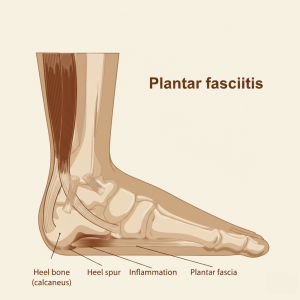

Topuk dikeni neden sabahları daha çok ağrı yapar?

Topuk dikeni ağrısının sabahları daha şiddetli hissedilmesinin temel nedeni, gece boyunca ayağın hareketsiz kalması ve yumuşak dokuların kısalıp sertleşmesidir. Özellikle topuk dikeniyle birlikte görülen plantar fasiya gerilimi, sabah ilk adımlarda ani ağrıya yol açar.

Gece boyunca ayakta ne olur?

Uyku sırasında:

Ayak uzun süre yük almadan dinlenir

Plantar fasya ve baldır kasları gevşek ve kısalmış pozisyonda kalır

Doku esnekliği geçici olarak azalır

Bu durum sabah kalkıldığında ayağın yere basmaya hazır olmamasına neden olur.

İlk adımlarda ağrı neden artar?

Sabah yataktan kalkıp ilk adımlar atıldığında:

Kısalmış plantar fasya ani şekilde gerilir

Topuk kemiği çevresindeki hassas bölge yük altına girer

Mikroskobik doku zorlanmaları oluşur

Bu nedenle ağrı genellikle ilk birkaç adımda en şiddetli düzeydedir.

Gün içinde neden azalır?

Yürümeye devam edildikçe:

Yumuşak dokular ısınır

Plantar fasya daha esnek hale gelir

Ayağın yük taşıma adaptasyonu artar

Bu da ağrının gün içinde azalmasına veya daha tolere edilebilir hale gelmesine yol açar.

Her sabah ağrısı topuk dikeni midir?

Hayır. Sabah ilk adım ağrısı topuk dikeninde tipiktir ancak:

Aşil tendonu problemleri

Plantar fasiit

Sinir sıkışmaları

gibi durumlarda da benzer şikâyet görülebilir. Bu nedenle doğru değerlendirme önemlidir.

Ağrıyı azaltmak için neler yapılabilir?

Sabah yataktan kalkmadan önce ayak tabanı ve baldır germe egzersizleri

Günlük hayatta uygun ayakkabı kullanımı

Ayağa uygun destekleyici tabanlıklar

Uzun süre çıplak ayakla sert zeminde yürümekten kaçınma

Sonuç

Topuk dikeni ağrısının sabahları artmasının nedeni, gece boyunca hareketsiz kalan ayak dokularının ilk adımlarda ani yüklenmeye maruz kalmasıdır. Bu durum topuk dikeniyle ilişkili ağrının en ayırt edici özelliklerinden biridir.